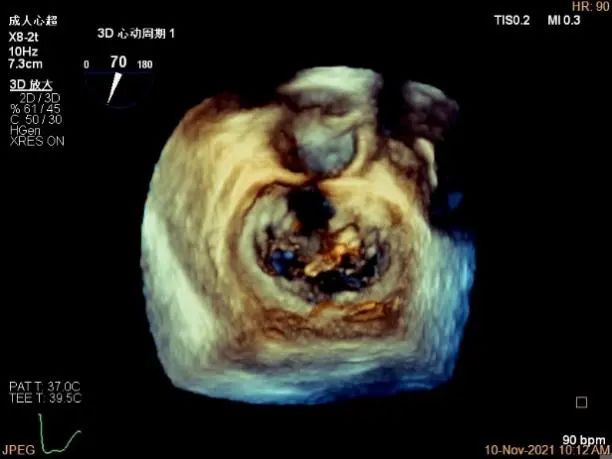

3D MV View:P1区瓣体瘤形成并中央型破裂孔,脱垂从P1到P2区,脱垂宽度13.1mm,破裂孔大小4.1×5.6mm

TEE Bicom view:主要病变区域为P1区,瓣叶中部可见连续性中断